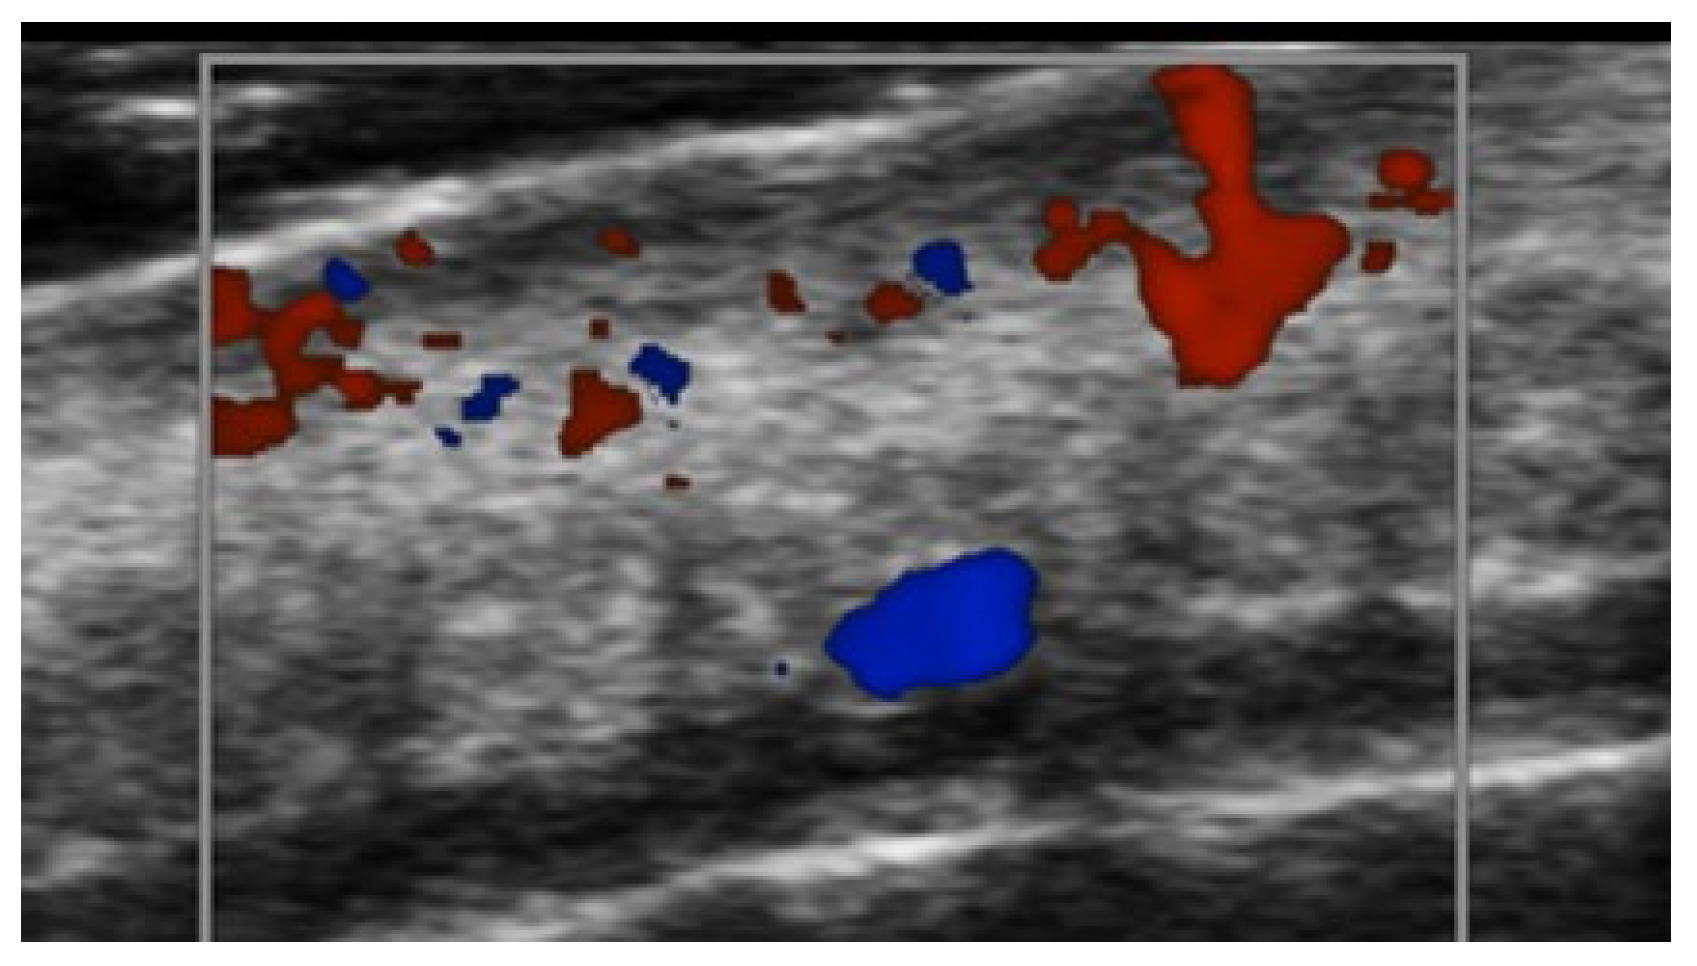

5. Specific Cutaneous Structure and Sites of Skin Disorders

6. Vascular Disorders